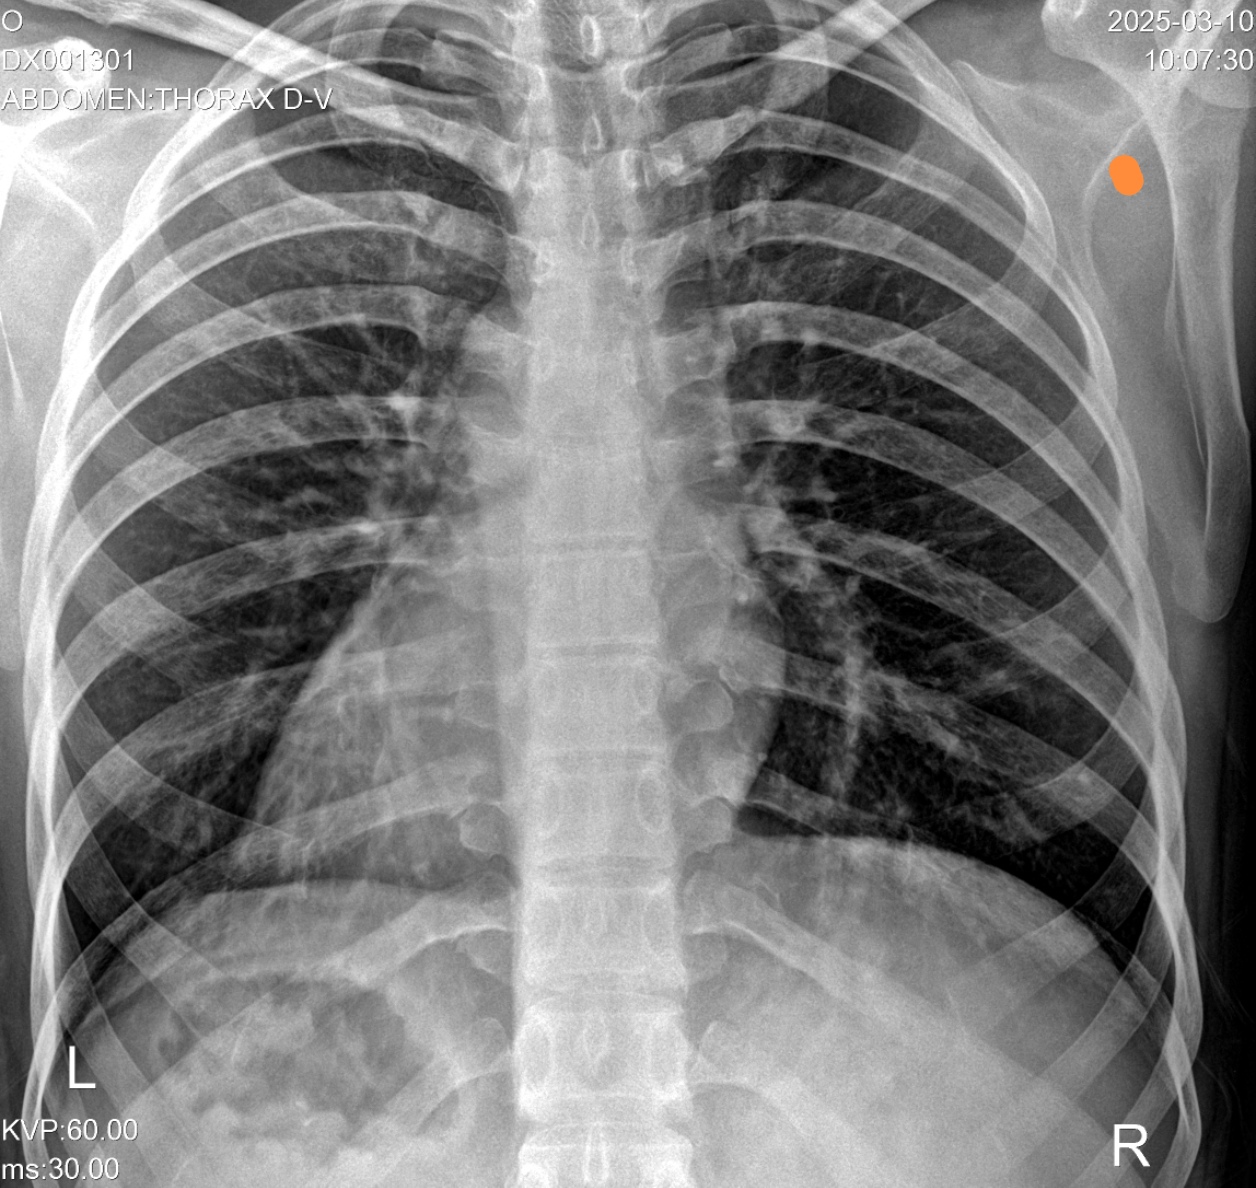

Женщина, 42 года. Рентгеновский снимок сделан на 4день болезни. Два врача сделали разные заключения.  Скажите, пожалуйста, есть ли пневмония?

Я бы не писал, а левый боковой не делали?

Андрей Юрьевич, только такие проекции. Боковых нет. Спасибо за ответ!

Я бы не писал

+1